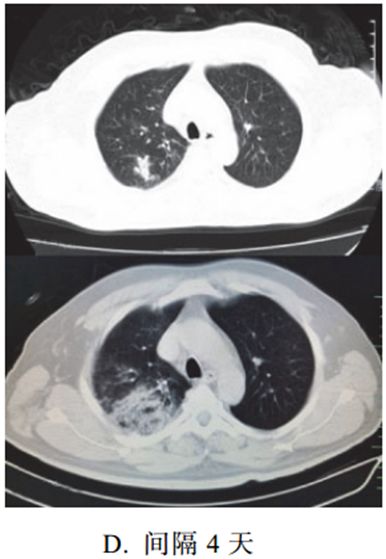

四、消散期征象

多数病例在 14 天后进入病灶消散期,表现为病灶逐步吸收,可遗留少许条索状高密度影,提示纤维化。少部分病例病程较短,影像可由早期表现直接进入消散期(图 2-17)。